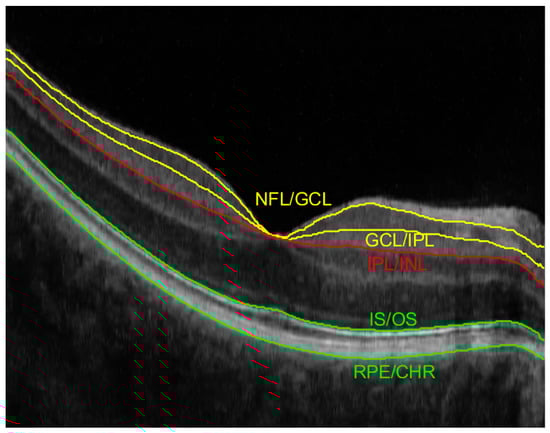

Figure 2 illustrates an example of an acquired OCT B-scan image with manual annotation of the borders for the above-listed layers. Two superficial vessels are visible as bright areas in the GCL layer (between the yellow lines illustrating NFL/GCL and GCL/IPL borders). Dark regions underneath, visible in the OS+RPE section (between the green lines of IS/OS and RPE/CHR borders) are the shadows of these vessels. The red line drawn in the B-scan image represents the lower boundary of the IPL layers, namely IPL/INL.

Figure 2.

Example of OCT B-scan with annotated retina layers borders used for fundus reconstruction (NFL/GCL, GCL/IPL, IPL/INL, IS/OS, and RPE/CHR).